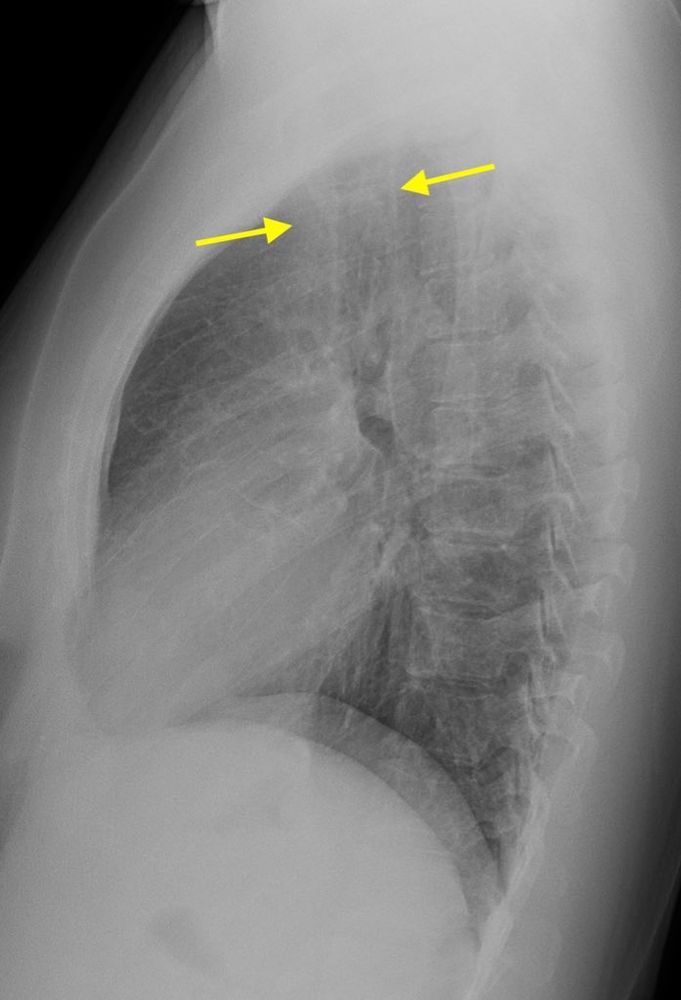

#LCAM Day 16 🫁🀍

🚺 mid 40s w fatigue, no smoking hx 🧐

PA/lateral CXR: RUL opacity.

Chest CT: solid R apical nodule w architectural distortion.

Bx: #EGFR+ adenoCA ➑️ curative surgery 🫁

Always doubleβœ… apices & have a high index of suspicion even in younger patients #AnyoneWithLungsCanGetLungCancer